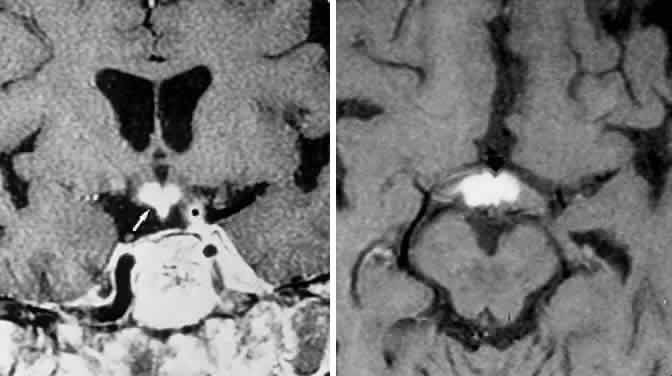

Fig. 2. Large prolactinoma. Original vision in the right eye (RE) was 8/200, left eye (LE) 1/200, with serum prolactin of 26,000 ng/ml and galactorrhea. Four months of bromocriptine reduced prolactin to 661 ng/ml, vision improved to RE 20/40, LE 20/50. At 3 years, vision was as follows: RE 20/30, LE 20/20; prolactin was 25.9 ng/ml. Enhanced magnetic resonance imaging. Sagittal (A) and coronal (C) images at diagnosis. Sagittal (B) and coronal (D) images at 2-year follow-up, showing dramatic shrinkage of the mass.